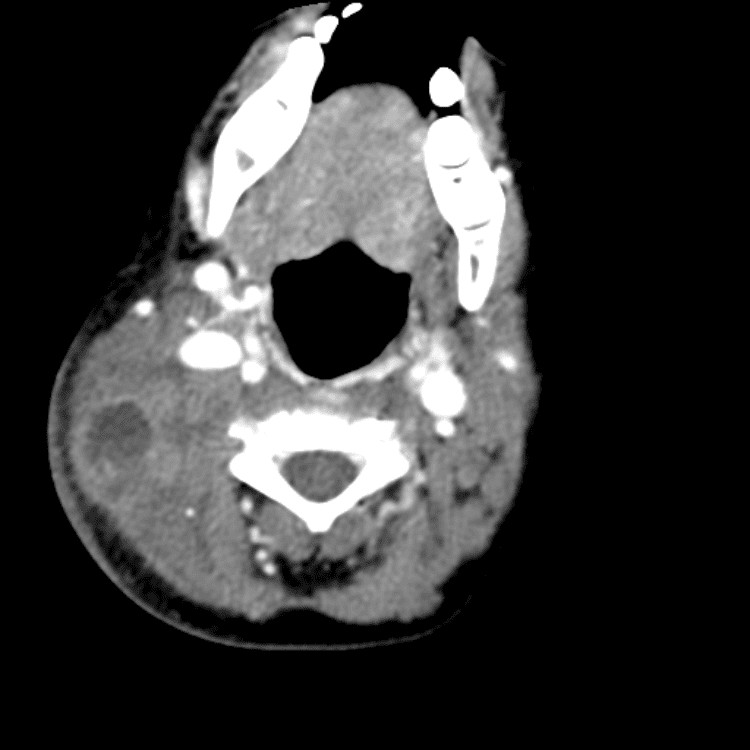

Head and Neck

Simulates call by including subtle or difficult cases and some normals.

27 cases